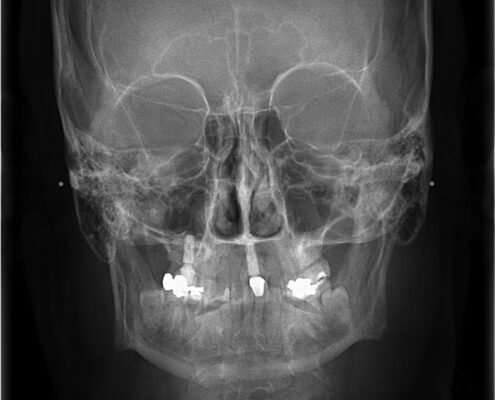

CEPH X-Ray

A cephalometric x-ray is a unique tool, which enables the dentist to capture a complete radiographic image of the side of the face. X-rays, in general, offer the dentist a way to view the teeth, jawbone and soft tissues beyond what can be seen with the naked eye. Cephalometric X-rays are extraoral, meaning that no plates or film are inserted into the mouth. Cephalometric and panoramic X-rays display the nasal and sinus passages, which are missed by intraoral bitewing X-rays.

Cephalometric X-rays are not as common as “full sets” or bitewing X-rays, but they serve several important functions:

- Provide information about “bad bites” or malocclusions.

- Identify fractures and other injuries to the teeth and jawbone.

After capturing cephalometric X-rays, the dentist will be able to see a complete side profile of the head. This can assist in orthodontic planning, and allow an immediate evaluation of how braces might impact the facial profile and teeth. Another common use for this type of X-ray is to determine specific measurements prior to the creation and placement of dental implants.